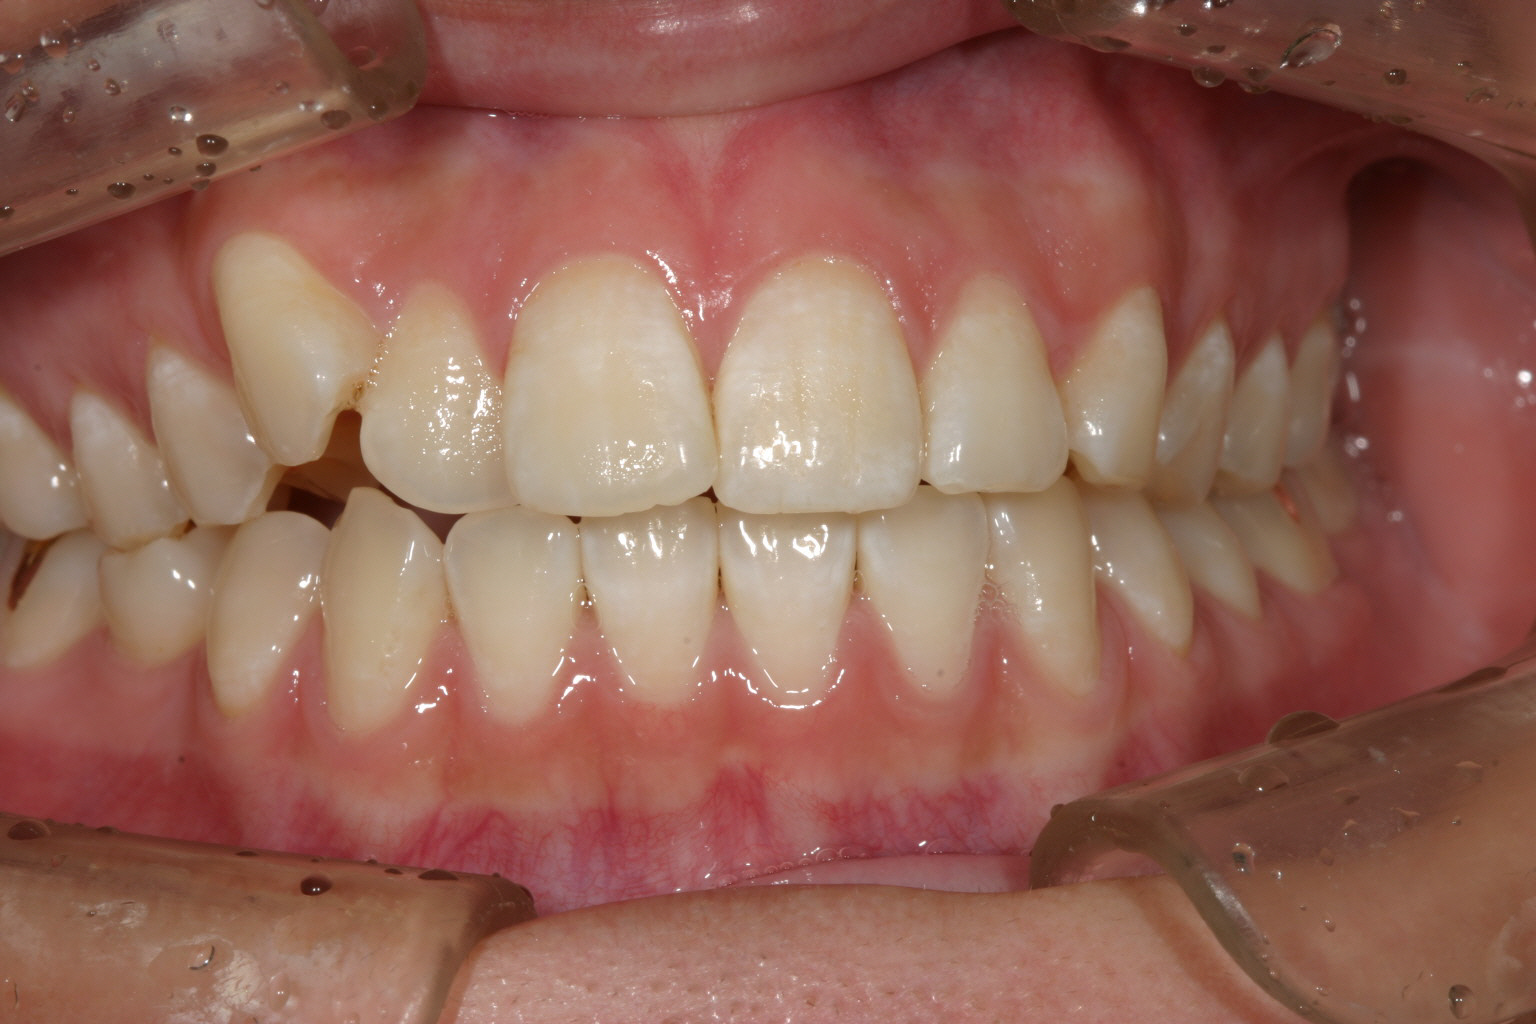

犬歯が飛び出して奥歯が上手く噛めていません。

右の犬歯の突出が気になりますね~ 口の中を見ると単に糸切り歯が出てるだけなんだから入れればいいと簡単に考えるのですが 犬歯が並ばないのは奥歯が全体的に前に来ている為に犬歯の入るスペースが無く外に飛び出しているんです。 その為部分ワイヤーを用いて犬歯以後の臼歯を全体的に遠心移動(後ろに送る事)しました。

下顎は一見綺麗に見えるのですが右の奥から3本目を見てください。 歯が90°回転しているのが見受けられます。 こういった歯をインビザライン単独で治療するにはかなり難易度が高く治療に相当の期間がかかり 結果として上手く戻らない事が多いです。 その為今回は部分ワイヤーを併用しました。